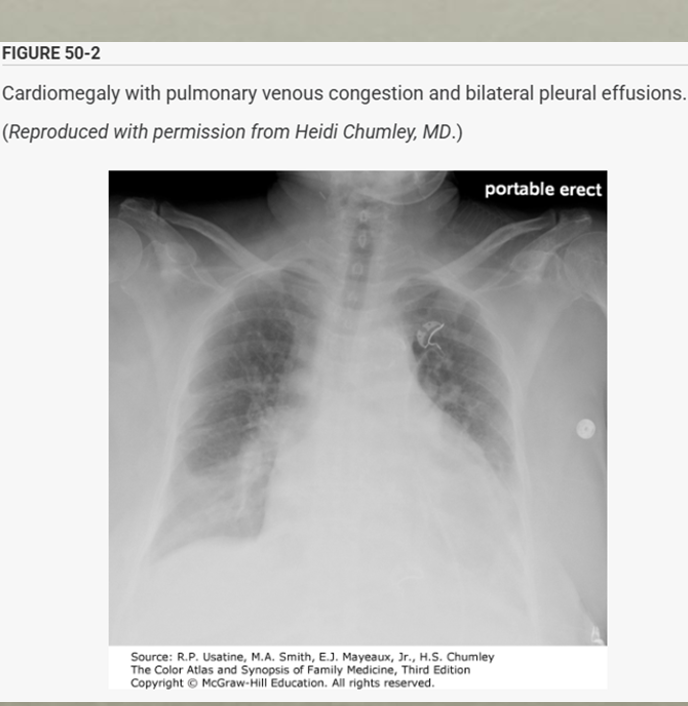

Common pathologies on Chest x-ray

HF

* Chest x-ray is a key tool in diagnosing CHF, showing signs of pulmonary congestion and cardiomegaly

* Findings var based on the severity of CHF (mild congestion vs, pulmonary edema)

* Key CXR signs include cardiomegaly, kerly B lines, pulmonary venous congestion (engorgement of upper lobe pulmonary veins due to increased L atrial pressure - early sign) and pleural effusions

notice the cardiac thoracic ratio